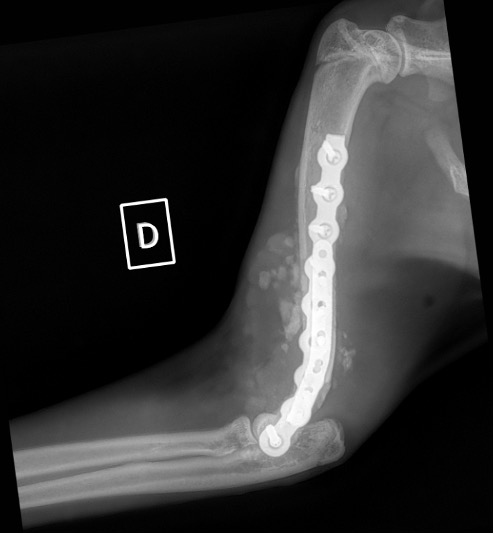

Exemple 1 :

Figure 1 : Pré-op

Figure 2 : Post-Op Immédiat

Figure 3 : Post-Op 1 Mois

Figure 3 : Post-Op 2 Mois

Notre préférence va vers le placement de deux plaques humérales : une médiale de la plus grande taille possible et l’autre latérale, généralement d’une taille inférieure à la première. Dans l’exemple 1 (chat européen), une plaque de 2 mm est utilisée médialement et une plaque de 1,5 mm latéralement. Dans l’exemple 2 (chien Malinois), une plaque de 3,5 mm est utilisée médialement et une plaque de 2,7 mm latéralement.